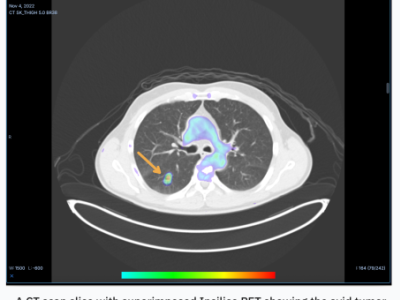

RADiCAIT adalah startup yang berasal dari Oxford yang mengembangkan teknologi menggunakan AI untuk mengubah CT scan menjadi gambar PET. Startup ini bertujuan untuk membuat pencitraan medis lebih terjangkau dan mudah diakses bagi pasien.

AI RADiCAIT Ubah CT Menjadi PET, Permudah Diagnosa Kanker Hidupkan Harapan Baru